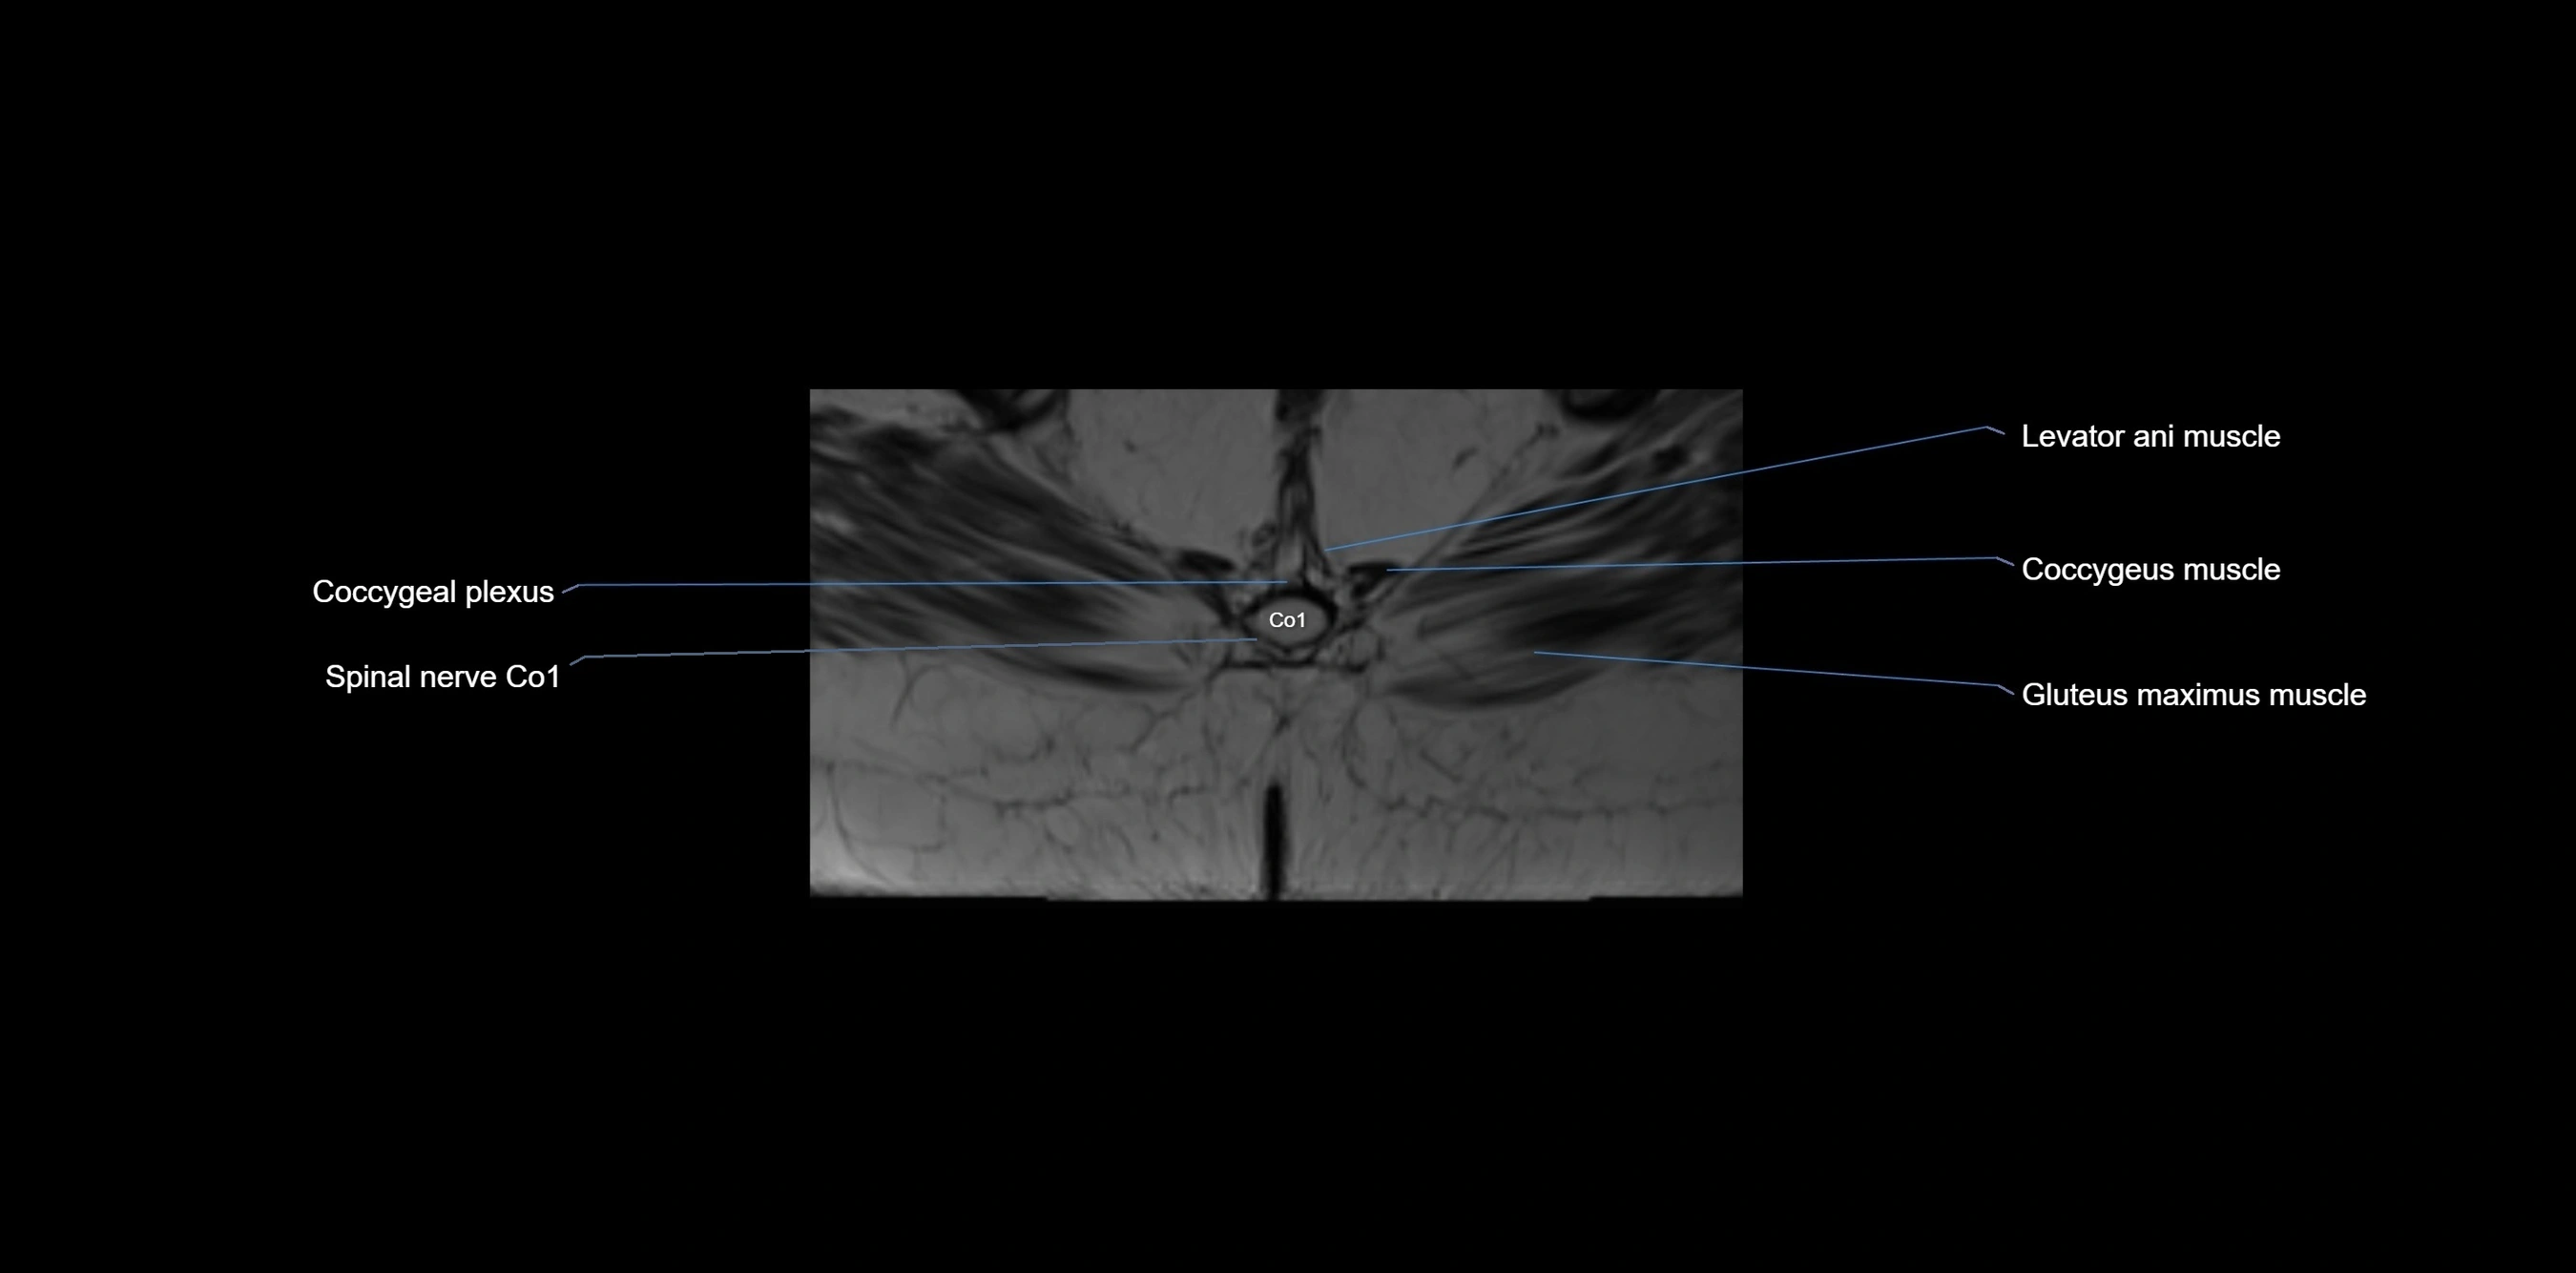

MRI Appearance

T1-weighted images:

• Cortical bone appears very low signal (dark); marrow shows intermediate signal

• Iliac fossa fat is bright against low-signal cortex

T2-weighted images:

• Cortical bone remains dark

• Marrow signal varies depending on fat content; edema or tumor shows hyperintensity

STIR:

• Suppresses fat, making bone marrow edema, fractures, or infiltrative lesions appear bright

• Excellent for trauma, sacroiliitis, and metastatic evaluation

MRI image

image